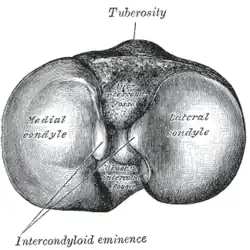

Kopf

Am kräftigsten ausgebildet ist das obere Ende, der Kopf (Caput tibiae), welcher zwei Gelenkknorren trägt (Condylus medialis und Condylus lateralis). Diese besitzen auf ihrer oberen Fläche eine überknorpelte Gelenkfläche (Facies articularis superior), die durch eine Erhöhung (Eminentia intercondylaris) in zwei Anteile getrennt wird. Die Erhöhung läuft in zwei getrennte Höckerchen (Tuberculum intercondylare mediale und Tuberculum intercondylare laterale) aus. Begrenzt wird sie vorne (ventral) und hinten (dorsal) durch zwei flache Gruben (Area intercondylaris anterior und Area intercondylaris posterior). Dort setzen die Kreuzbänder und die Haltebänder der Menisken an. Die gesamte obere Fläche des Schienbeines wird als Schienbeinplateau bezeichnet und bildet mit den Knorren des Oberschenkelknochens (Femur) das Kniegelenk. Am seitlichen Umfang des nahezu senkrecht stehenden Knochenrandes findet sich die Gelenkfläche (Facies articularis fibularis) für den Wadenbeinkopf (Caput fibulae), mit dem sie die Articulatio tibiofibularis bildet.